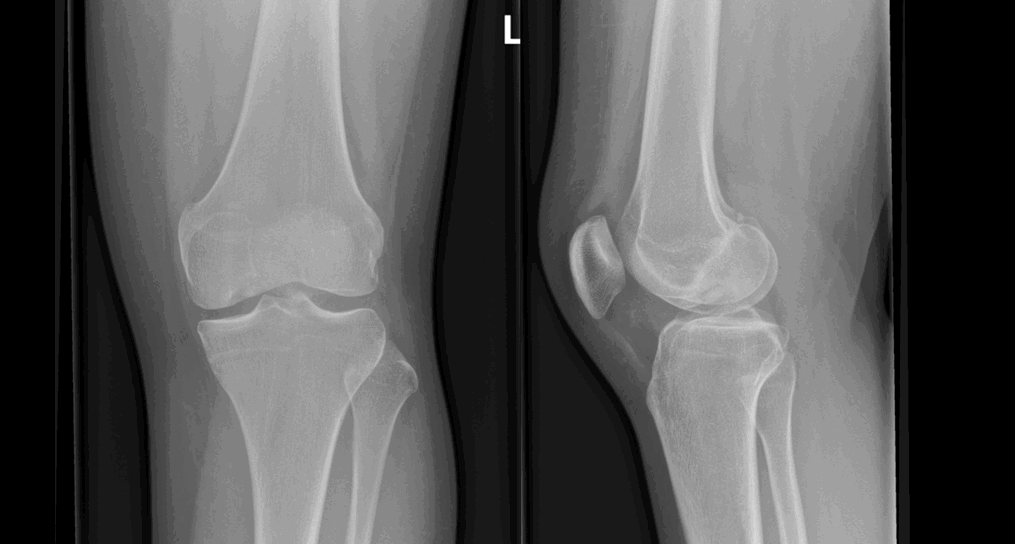

Age 18 female. Referral from GP. History: painful left knee

Findings:

Defect in articular surface of medial femoral condyle

Well-circumscribed bony fragment projected over intercondylar region representing detached osteochondral fragment

No joint effusion

Likely diagnosis is osteochondritis dessicans. DD osteochondral #

Management:

OP referral to orthopaedic surgery for further management

Comments: Can be managed conservatively or by surgery

| Sample answer | Answer type | Explanation of scoring allocation |

|

There is an osteochondral defect in the lateral aspect of the medial femoral condyle. There is a bone fragment centrally within the joint space. No joint effusion. Knee MRI and Orthopaedic referral |

High scoring answer |

This answer would score highly because the candidate has identified an osteochondral defect in the medial femoral condyle as well as the loose bone fragment. |

There is lucency projected over the lateral femoral condyle of left femur in keeping with an osteochondral defect. A cortical fragment seen in the intercondylar space. No large knee joint effusion identified. Normal alignment Orthopaedic referral and further assessment with MRI may prove beneficial. |

Mid scoring answer |

This answer would not score so highly because the candidate has reported the abnormality, but they have stated that the osteochondral defect is in the lateral rather than the medial femoral condyle. The examiner cannot be sure whether this is a typographical error or the candidate missed the medial condylar defect and over-diagnosed a defect in the lateral femoral condyle. |

Well-defined lesion in the right distal femur, with sclerotic margins and a narrow zone of transition. No periosteal bone formation. Referral to orthopaedics due to pain. No concerning imaging features so no further investigation needed. |

Low scoring answer |

This answer has scored low marks for an incorrect diagnosis. |